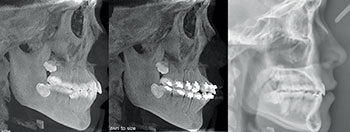

The second case is a 17-year-old male. Despite the crowding and protrusion, I felt that non-extraction treatment had a reasonably good chance of success. I initially flipped his upper incisor brackets in anticipation of needing negative torque. However, the progress records from the pan/repo/ceph appointment at seven months revealed to me that continuing with the non-extraction plan in my hands was not prudent. I did not feel confident that, even with the prospect of safely pushing the limits of IPR and negative torque, I would be able to position his upper incisors in an ideal AP and labiolingual position. The decision was made at that appointment to un-flip (reposition) the upper incisor brackets and refer for the extraction of his upper first bicuspids and lower second bicuspids. The treatment was completed in 25 months, resulting in a favorable position of his upper incisors within his face and smile.